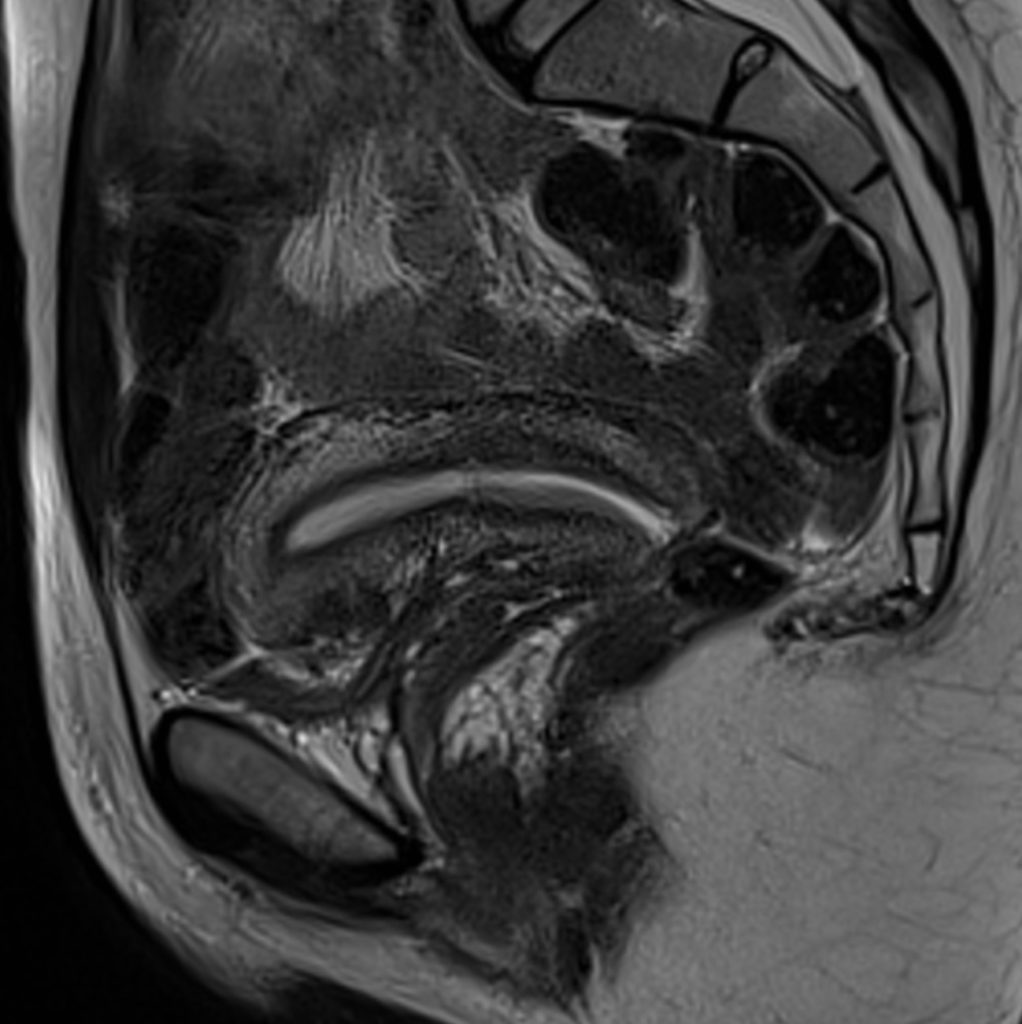

IRM pelvienne L'IRM est un examen non irradiant, sans risque, qui est très utile pour le diagnostic et le bilan d'une endométriose puis Comment se déroule l'examen IRM pelvienne dynamique ?

PPT IRM PELVIENNE Pour les nuls PowerPoint Presentation ID5221314. Quels organes Voit-on sur un IRM pelvien ? Qu'est-ce qu'une IRM pelvienne Comment se préparer à une IRM pelvienne ? "En fonction de la demande faite par le médecin généraliste ou spécialiste, le radiologue décidera s'il est nécessaire d'effectuer un lavement évacuateur quelques heures avant l'examen, s'il faut être à jeun (généralement six heures avant l'examen) ou s'il faut avoir une vessie pleine ou vide", répond la spécialiste.